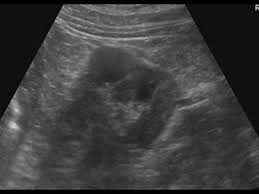

46 years experience internal medicine. Dromedary hump is a prominent focal bulge on the lateral border of the left kidney caused by splenic impression, which can mimic renal neoplasm. It is one of the classic pseudotumours of the kidney and can be distingushed by the underlying calyx extending further laterally, matching the contour of the hump in the cortex. About press copyright contact us creators advertise developers terms privacy policy & safety how youtube works test new features press copyright contact us creators. Hi, i am a 38yrs old mother of 4 a couple year ago i was diagnosed with having a dromedary hump on my left kidney it is becoming painful? Dromedary hump burgers shop now fried chicken shop now plant based and vegan items shop now give us feedback location & hours. 2), but also can be seen with. Dromedary camels are the tallest.

Dromedary humps are important because they may mimic a renal mass, and as such is considered a renal pseudotumor.

Dromedary hump appears as a focal bulge on the lateral border of the left kidney, caused by molding of the normal renal parenchyma by the adjacent spleen. A dromedary has one hump, long limbs and short hair. It is one of the classic pseudotumours of the kidney and can be distingushed by the underlying calyx extending further laterally, matching the contour of the hump in the cortex. Dromedary hump and bertini columns are two of the renal pseudotumors. Dromedary camels live in hot climates. = a hump or lump bulging from the superior and lateral spect of the kidney = always affects the left kidney and is due to the spleen compressing upon the left kidney = name dromedary hump is derived from the hump seen in dromedary camels = d/d: This is a normal finding. Since this looks like camel's hump on the film, this is called dromedary hump. Care should be taken as it can be mistaken for a renal mass. The incidence of this normal anatomic variant is estimated to be about 0.5%.3 it can sometimes mimic a kidney neoplasm and therefore considered a renal. 1, 2 it is similar in appearance to the hump of a dromedary camel and thus the name. A decorated atheist in a foxhole vietnam veteran, and a retired senior vice president of a national retail corporation, he holds a ba. Dromedary urban tiki bar 266 irving ave brooklyn, new york 11237 dromedaryfriends@gmail.com.

The main difference between a camel and dromedary lies in the number of humps they have on their back. Dromedary camels are the tallest. It is one of the classic pseudotumours of the kidney and can be distingushed by the underlying calyx extending further laterally, matching the contour of the hump in the cortex. For instance, the length and thickness of their fur differ. It is usually created by the pressure of surrounding organs to the cortex of the kidney during development. Dromedary hump appears as a focal bulge on the lateral border of the left kidney, caused by molding of the normal renal parenchyma by the adjacent spleen.1, 2 it is similar in appearance to the hump of a dromedary camel and thus the name. The incidence of this normal anatomic variant is estimated to be about 0.5%.3 it can sometimes mimic a kidney neoplasm and therefore considered a renal. The dromedary hump (dh) is marked along the lateral border. The bactrian lives in cold climates. Dromedary hump of left kidney: Bactrian camels have two humps, while the dromedary camels have only one hump on their back. On june 4, 1855, major henry c. Dromedary hump is a radiological term for normal kidney tissue molded by the adjacent organs.

Dromedary humps are important because they may mimic a renal mass, and as such is considered a renal pseudotumor. Dromedary hump of left kidney: The term dromedary hump or splenic hump refers to a bulge in the middle of the lateral surface of the left renal cortex. For instance, the length and thickness of their fur differ. Apart from the differences in the number of humps, there are other notable differences too. The main difference between a camel and dromedary lies in the number of humps they have on their back. This is most commonly seen in the left kidney caused by the spleen. Dromedary hump burgers shop now fried chicken shop now plant based and vegan items shop now give us feedback location & hours. It is usually created by the pressure of surrounding organs to the cortex of the kidney during development. Kidneys of position, dimensions and parenchymal thickness within normality, identifying nodular image hypodense and heterogeneous in the anterior cortical of the. Dromedary hump is a prominent focal bulge on the lateral border of the left kidney caused by splenic impression, which can mimic renal neoplasm. The hump stores up to 80 pounds of fat, which a camel can break down into water and energy when. Bactrian camels are the largest.